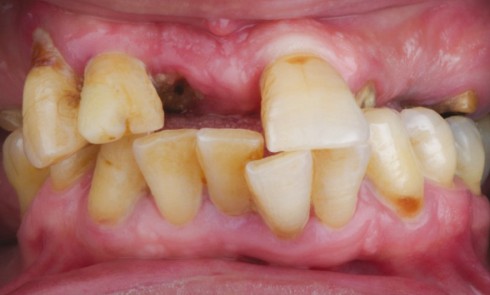

Présentation du cas (fig. 1 à 9) Madame J, âgée de 49 ans, nous est adressée par son occlusodontiste pour...